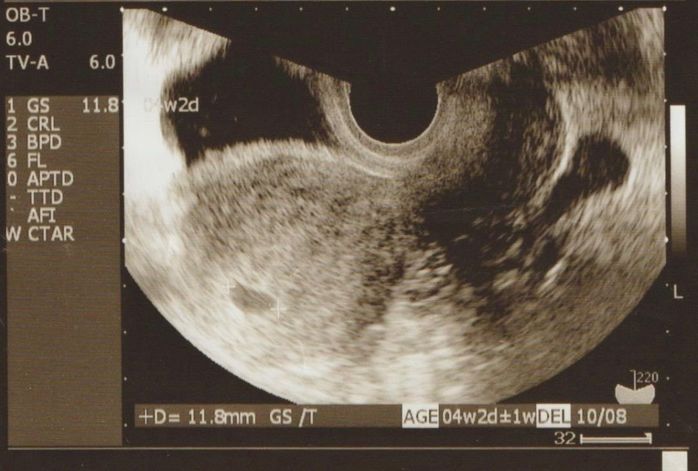

胎嚢が確認できました - 妊娠5週目のエコー写真

D=11.8mm 胎嚢が確認できました

妊娠検査薬で陽性反応が出てから3日後に一人で受診。胎嚢の確認ができ妊娠していることがちゃんと分かると、先生の前で嬉しくて涙してしまいました。「私たちの元へやってきてくれてありがとう」という思いが溢れてくるとともに、一度流産の経験があったため、「もしまた流産してしまったら…」という不安な気持ちも一緒に押し寄せてきました。